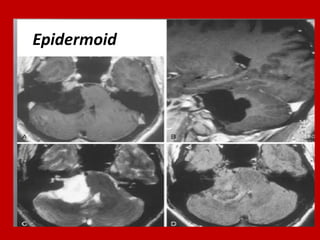

Epidermoid